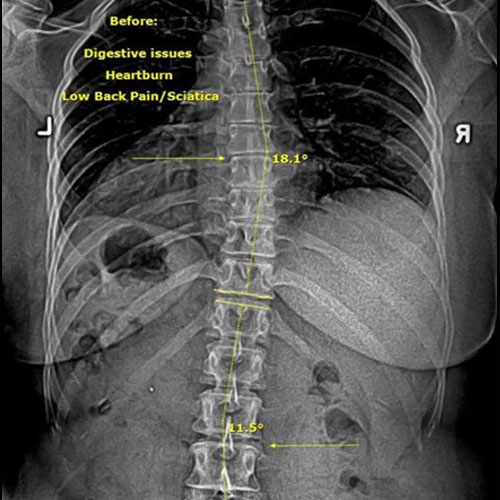

In this case, initial cervical spine X-rays revealed a significant loss of normal neck curvature, a condition that places excessive strain on the spine and nervous system. When the cervical curve is reduced, the head shifts forward, increasing stress on spinal joints, discs, and nerves — often leading to chronic neck pain, headaches, migraines, and neurological symptoms.

Before Chiropractic Treatment: The patient’s X-rays showed a flattened cervical curve, meaning the neck was no longer supporting the head in its ideal position. This type of misalignment is commonly linked to long-term spinal degeneration, nerve irritation, and persistent symptoms that don’t resolve with medication alone.

When spinal structure is compromised, the body is forced to compensate — and over time, those compensations break down.